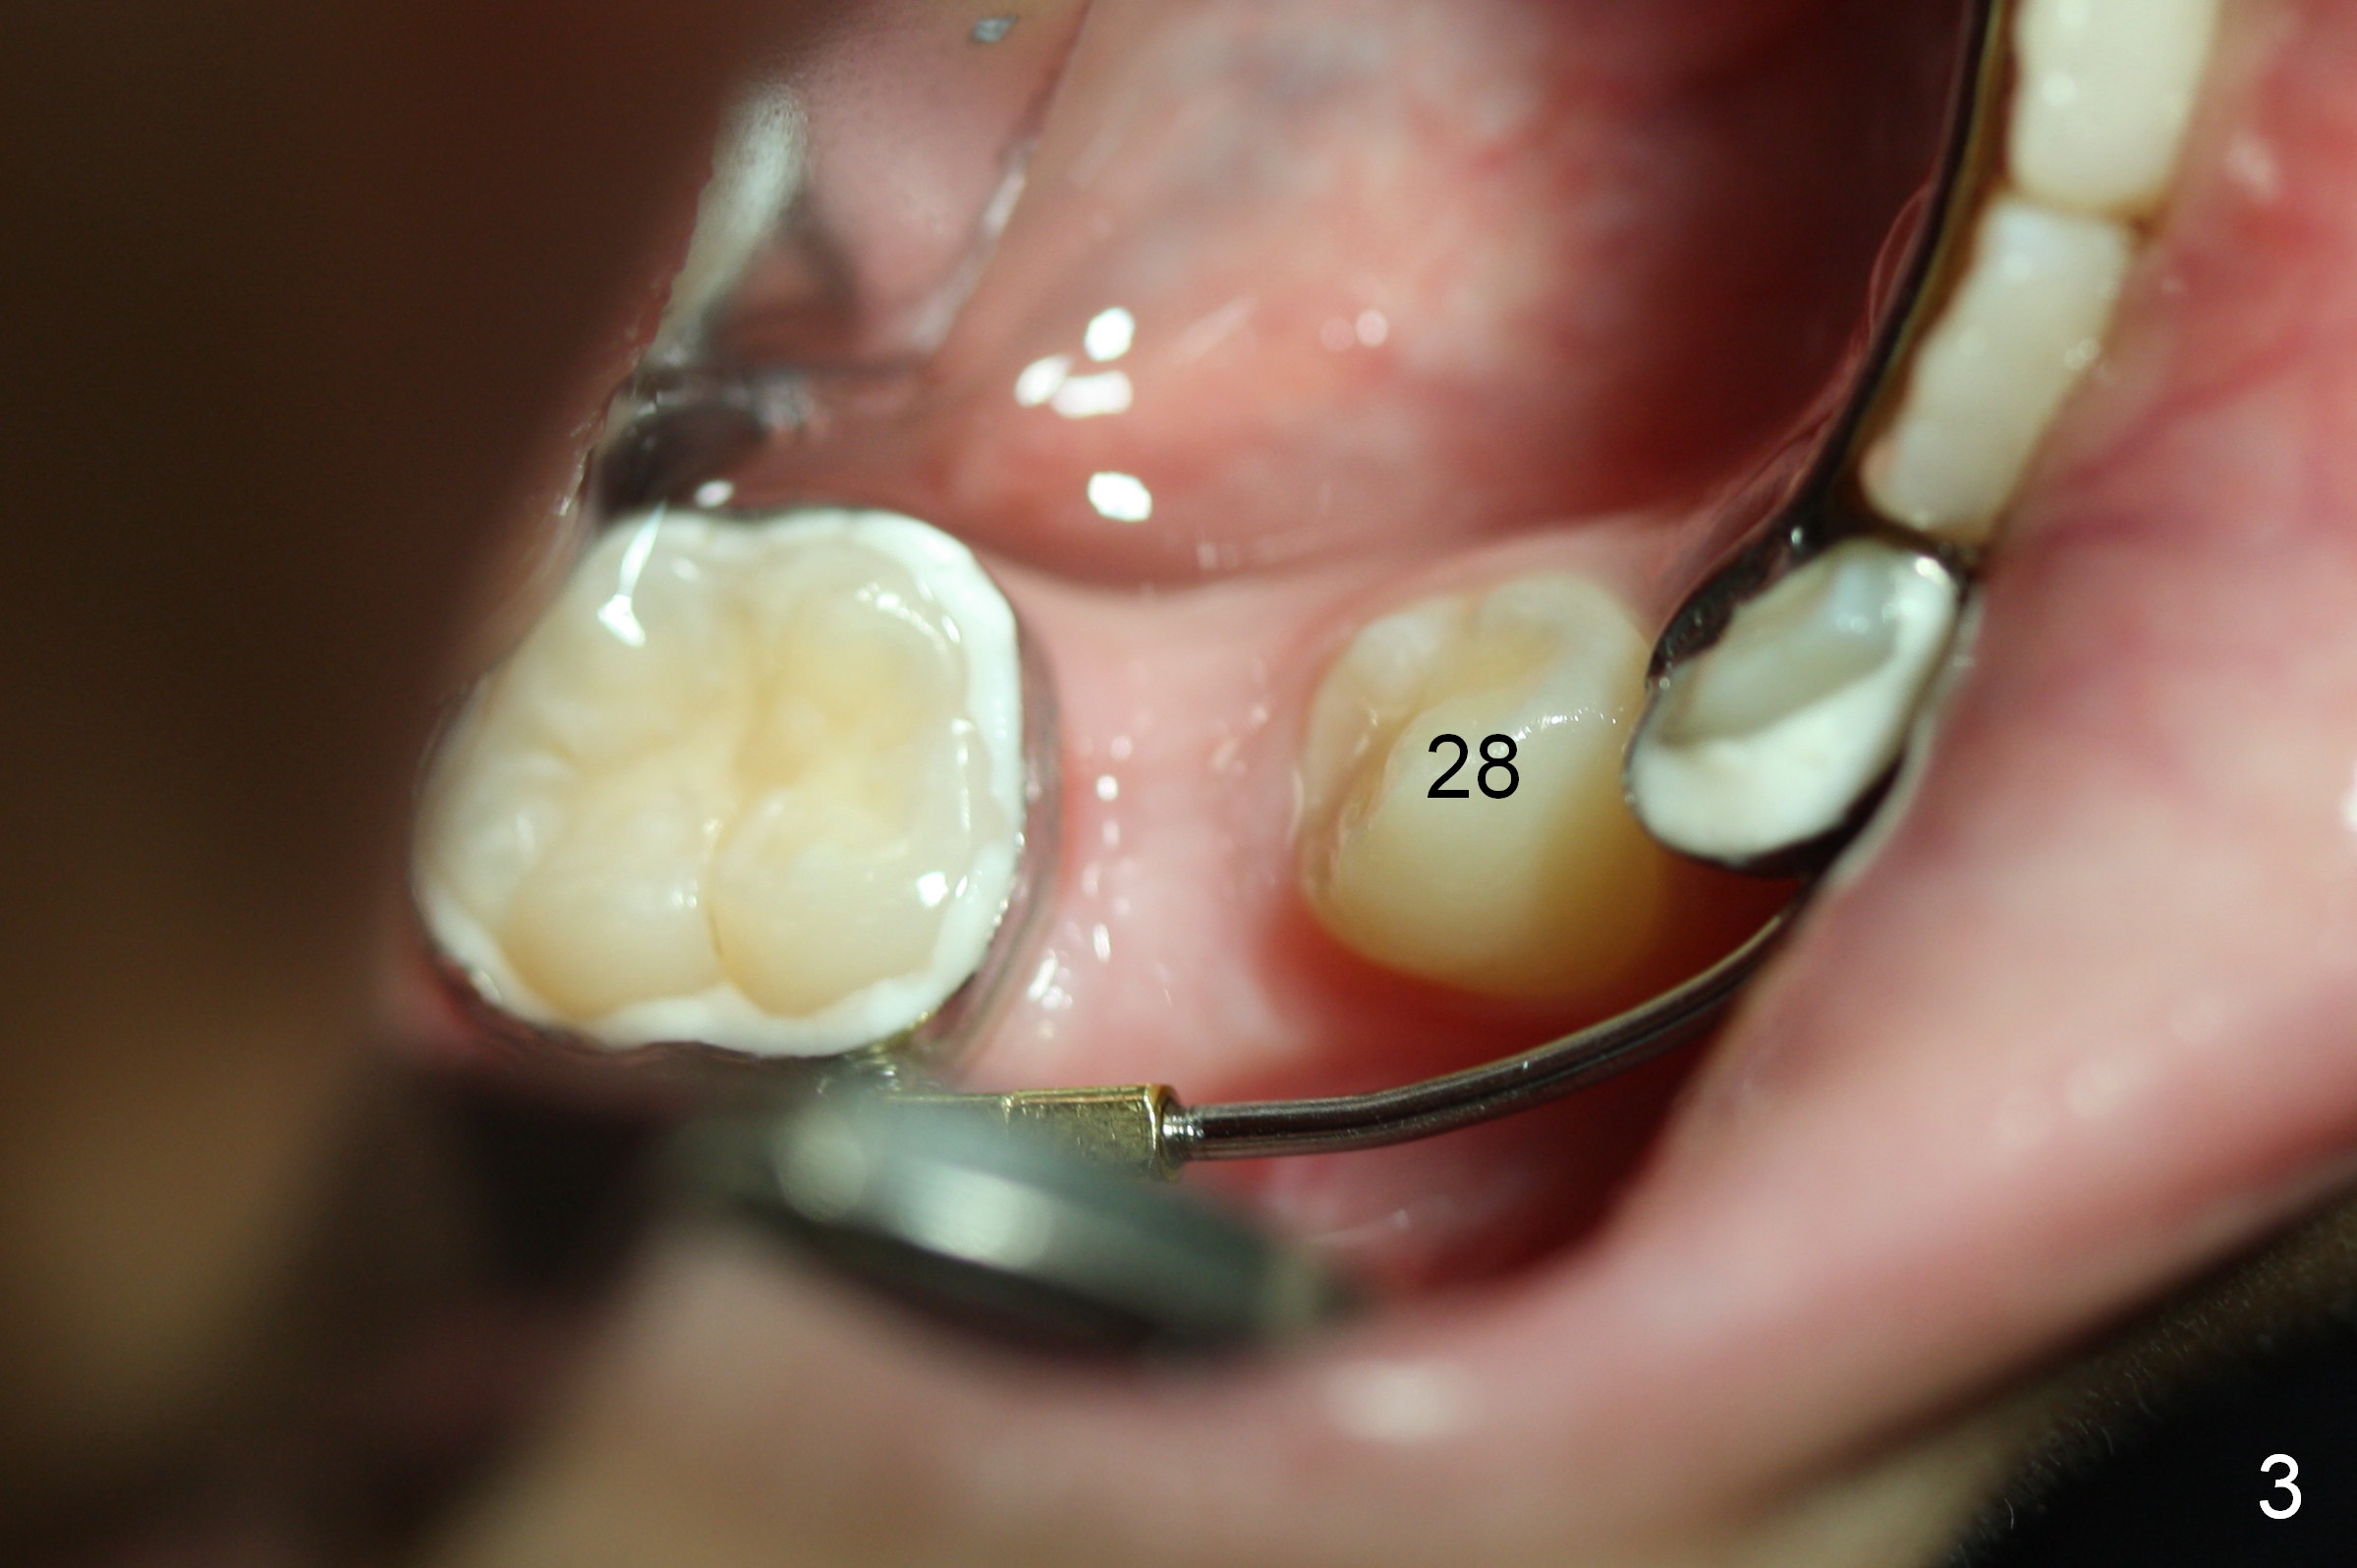

A 9-year-old girl has 2 space issues (missing #26 (*) and mesial shift of #30 (arrow), Fig.1). After extraction of S and T (Fig.2), a space regainer is fabricated. In 3 months, the tooth #28 is erupting (Fig.3); the regainer is being activated. Next visit, check anterior overjet. When the regainer is activated, the tooth #27 feels being pressured. The lower anterior teeth may be pushed anteriorly.